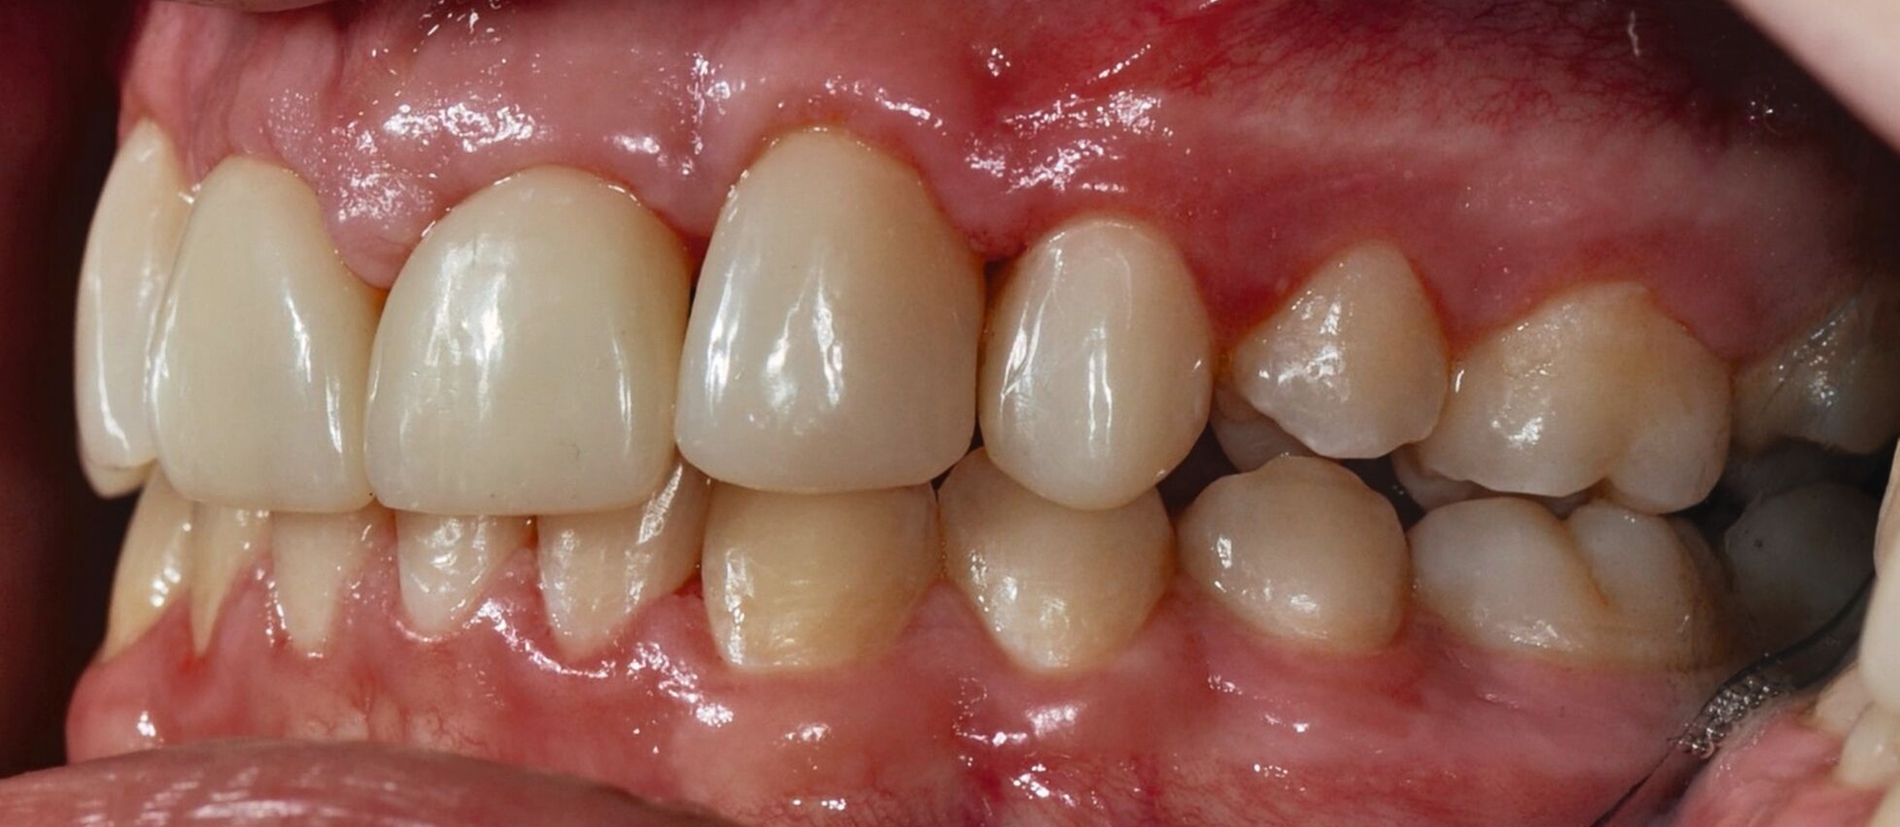

Auch bei einer Kontrolluntersuchung drei Jahre nach restaurativer Therapie sind die Versorgungen in situ, intakt, und das Parodontium zeigt keine entzündlichen Veränderungen. Trotz Anfertigung der Retentionsschienen fällt ein beginnendes Diastema mediale auf (Abbildung 4). Der Patient gibt auf Nachfrage an, die Schienen nicht regelmäßig getragen zu haben. Ihm wird die Möglichkeit eines Diastemaschlusses durch eine erneute Zahnformkorrektur angeboten. Da ihn die entstandene Lücke jedoch subjektiv nicht stört, entscheidet er sich zunächst gegen eine restaurative Korrektur.